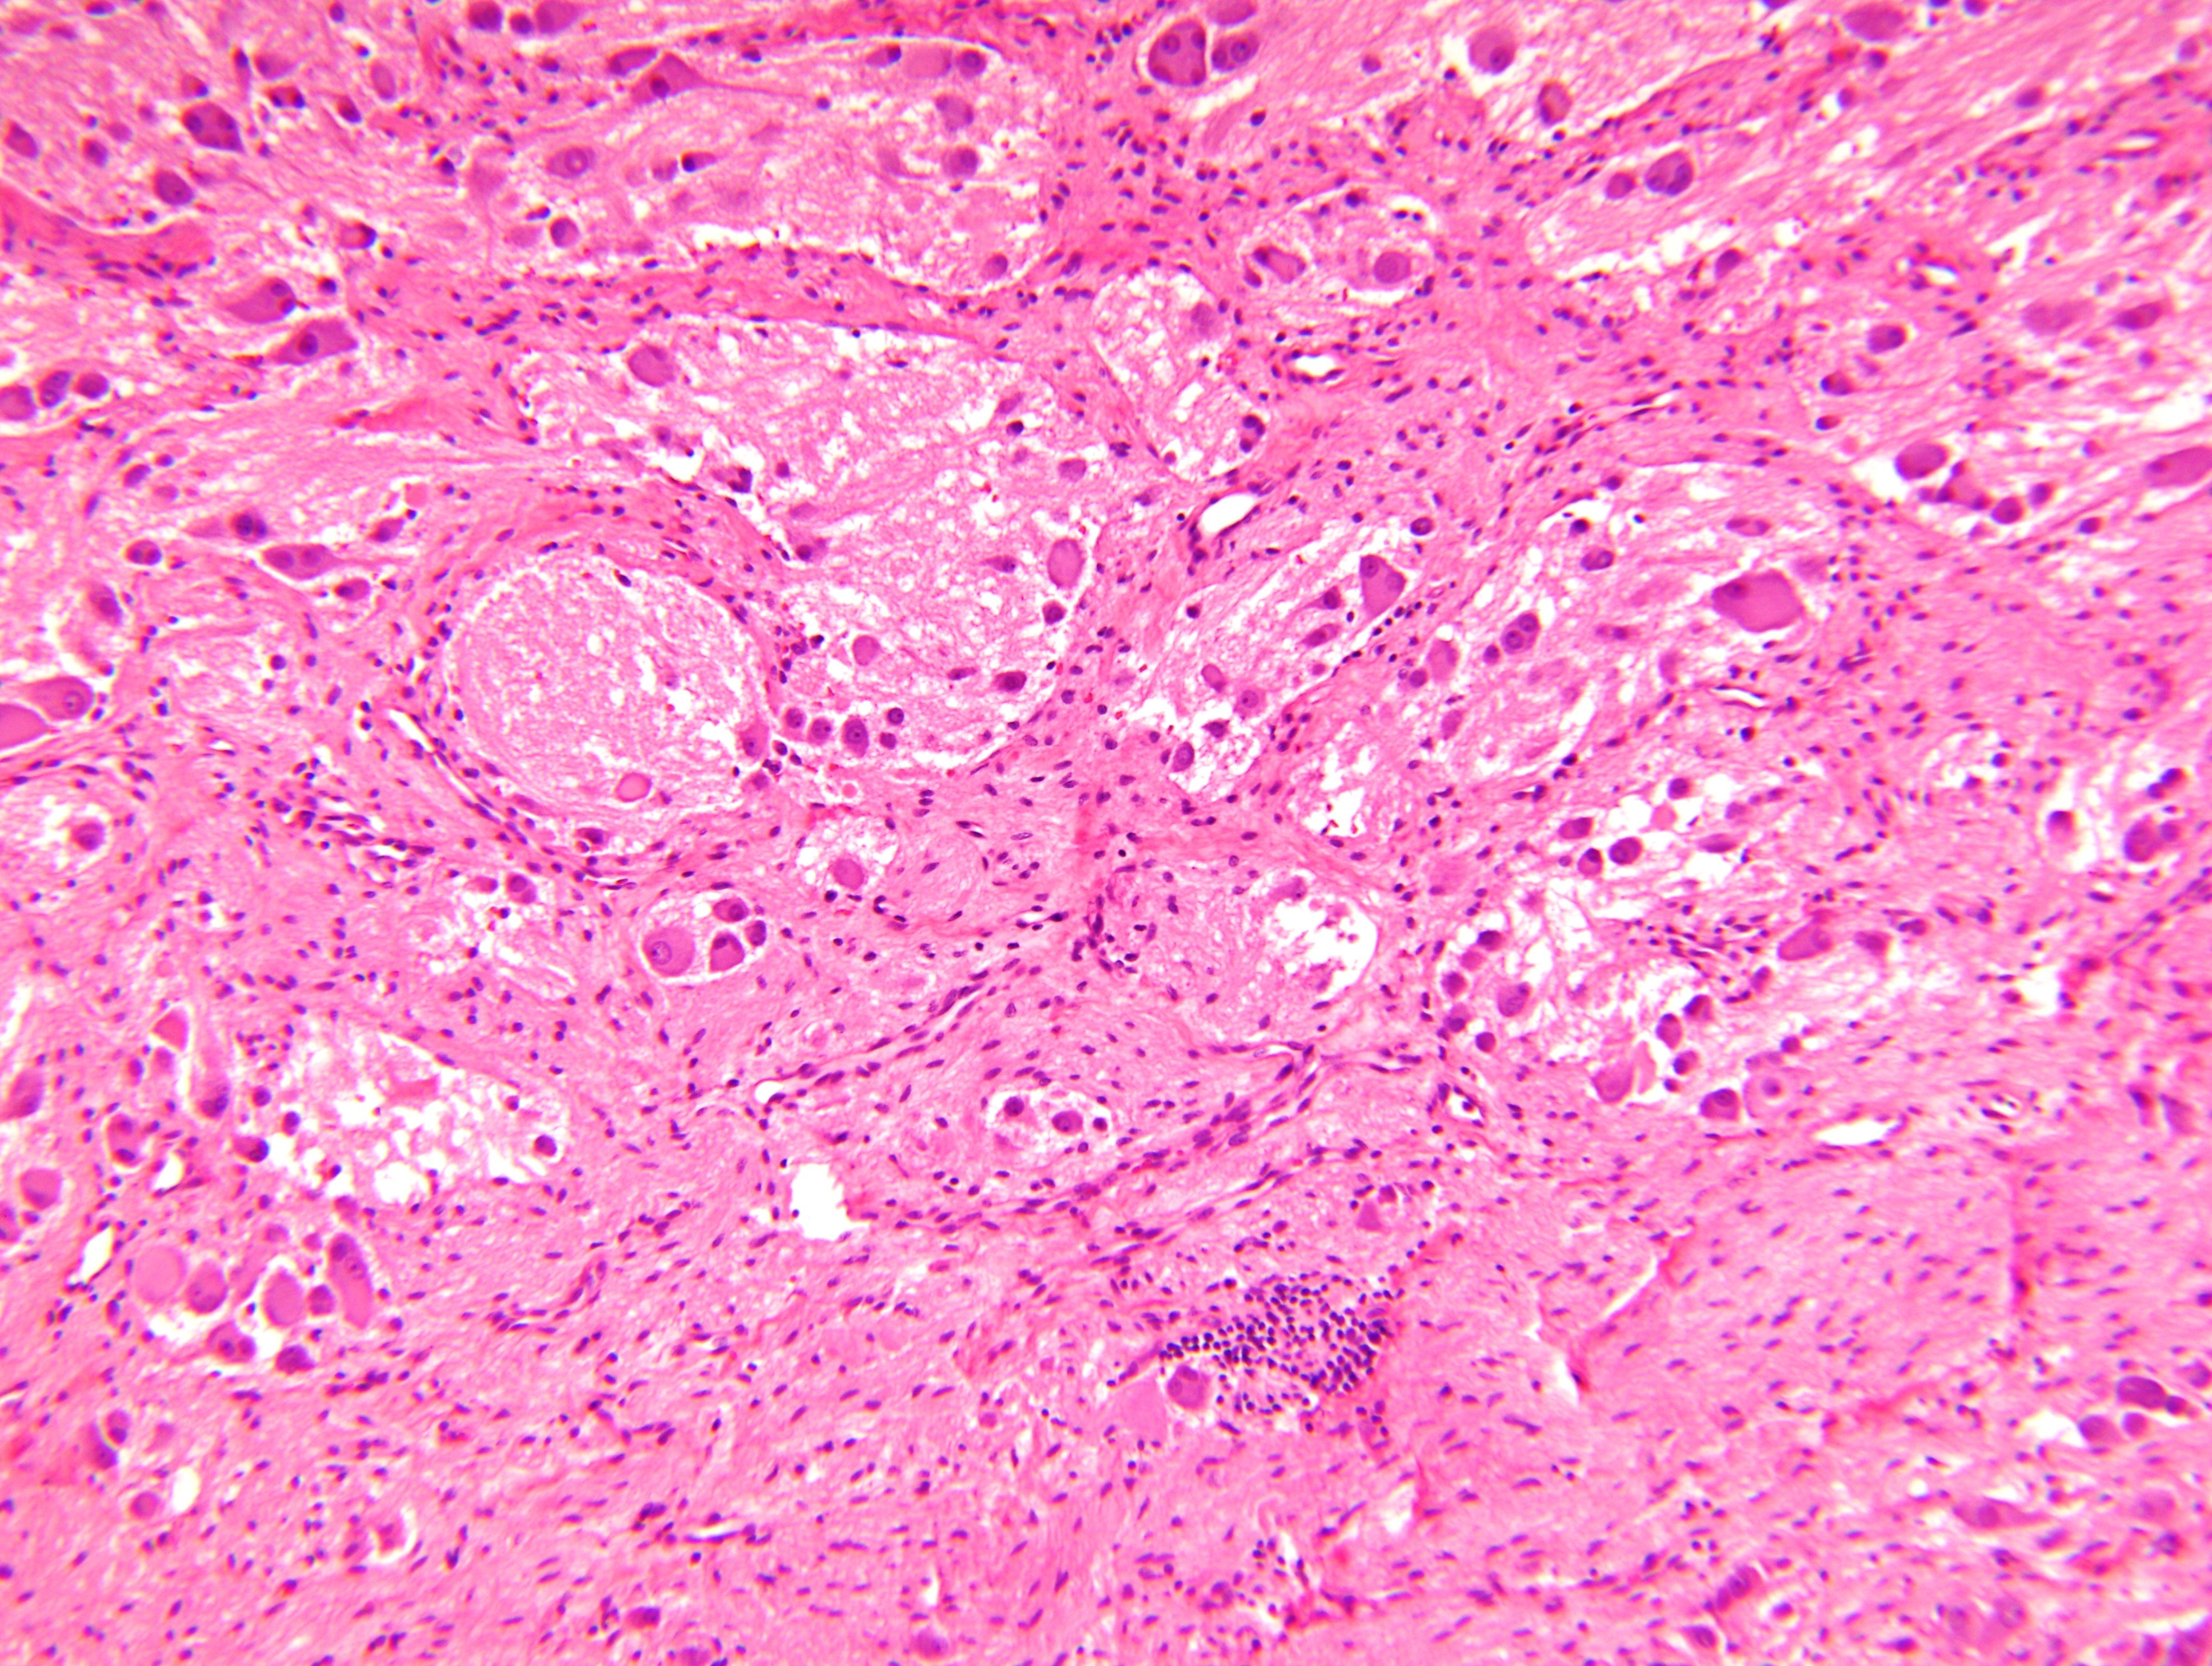

Microscopic (histologic) description

- Architecture: lobular, diffuse / solid, organoid

- Neuroblasts

- Homer Wright pseudorosettes = circular, ovoid, angular zones of pale staining neuritic cell processes surrounded by tumor cell nuclei; may rarely palisade

- Ganglion cells

- Abundant granular eosinophilic cytoplasm (Nissl substance = rough endoplasmic reticulum)

- Distinct cell borders

- Nuclear enlargement, eccentric nuclei, prominent nucleoli

- May see neuromelanin pigment (brown, finely granular; rarely present), cystic degeneration, hemorrhage, dystrophic calcification

Microscopic (histologic) images

Contributed by Carmen Perrino, M.D. and Debra L. Zynger, M.D.

Nodular type